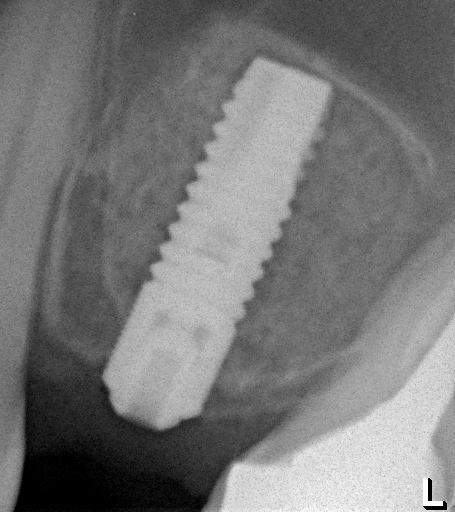

Оптимальное расстояние от дна гайморовой пазухи до верхней точки альвеолярного гребня верхней челюсти, при котором возможна стабилизация импланта длиной 10-11 мм – не менее 3-4 мм. Однако, в некоторых случаях имплантат длиной 11 мм удается стабилизировать в меньшем объеме костной ткани (рис 46, 47, 48):

Рисунок 46, 47, 48. Стабилизация импланта при толщине костной ткани менее 3 мм: слева – установка импланта после синуслифтинга, в центре – заполнение субантрального пространства спейсером, справа – рентгенологический контроль.